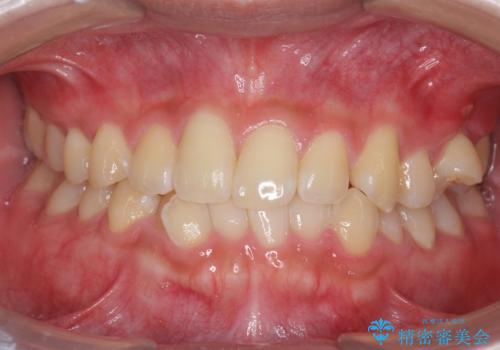

- 10代男性

- コンタクトスポーツをするためマウスガードを作りたいとのことで来院された患者様です。